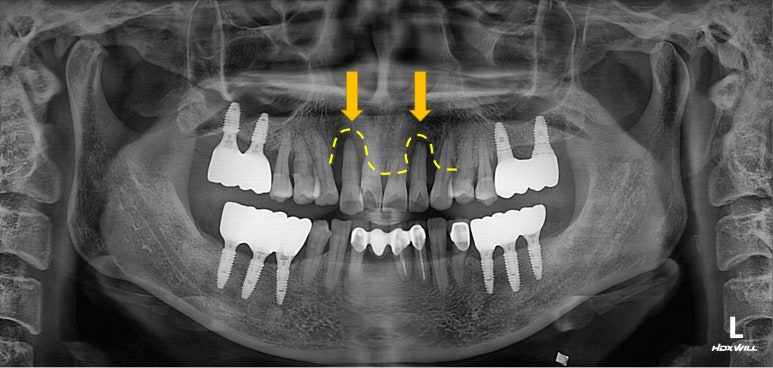

엑스레이를 보시면, 양쪽 위턱 가쪽 앞니가 거의 잇몸뼈와 분리되어 둥둥 떠있는 모습을 보실 수 있습니다.

잘 모르시겠다면, 제가 표시해드리겠습니다..!!

점선이 실제 잇몸뼈의 높이를 나타내고 있습니다.

노란 화살표로 표시한 두개의 위턱 측절치가 남아있는 뼈 없이 둥둥 떠있는 모양이에요.